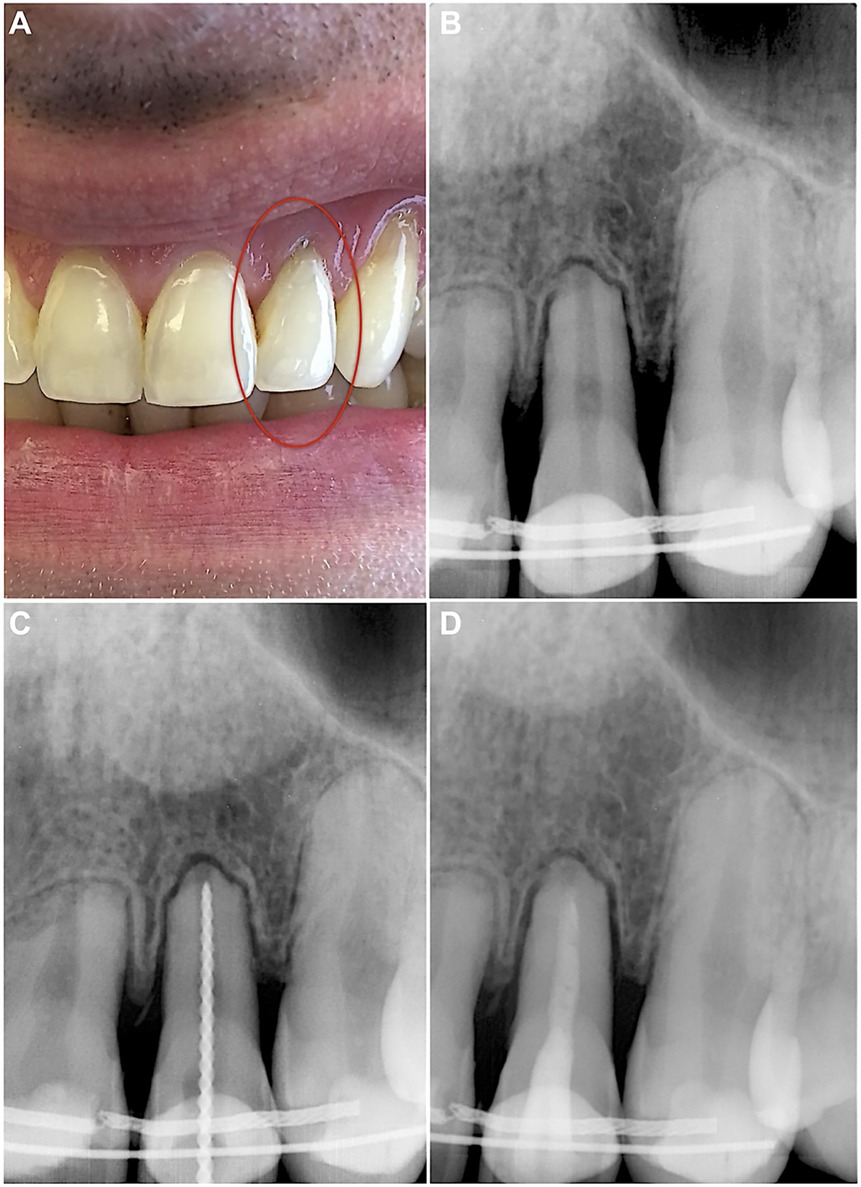

The patient returned for examination 14 months later, reporting that he accidentally fell down and re-injured his upper lip and front teeth 2 weeks ago. After the accident, the patient took Ibuprofen for 2 days to manage the pain. The patient had no complaints other than mild discomfort in tooth 22. Upon examination, no signs of endodontic pathology were observed. The retention wire was intact, and tooth 22 was slightly tender to percussion. The periapical radiograph revealed a uniformly and slightly widened periodontal ligament (Figure 3A). A follow-up was scheduled 1 month later to monitor the situation.

Figure 3. (A) Periapical radiograph performed during examination 2 weeks after the secondary dental trauma. (B) Eighteen-month follow-up periapical radiograph demonstrating changes in homogeneity of the root canal filling, along with a periapical lesion on tooth 22. (C) Intraoperative periapical radiograph for retreatment WL determination. (D) Intraoperative periapical radiograph after placing Biodentine in the apical and middle thirds of the root canal.

The patient did not adhere to the follow-up protocol and returned 18 months later, reporting spontaneous, throbbing pain and sensitivity on touching tooth 22. Upon examination, no extraoral or intraoral changes were observed. However, the tooth 22 was acutely tender to percussion. The periapical radiograph revealed a periapical lesion, along with a noticeable disintegration and decreased homogeneity of root canal filling (Figure 3B). Endodontic retreatment of the tooth was immediately initiated by removing the coronal restoration under the aforementioned protocol of local anaesthesia, isolation and disinfection. The procedure was performed under a dental operating microscope, which again revealed no signs of cracks or fractures. The dissolved MTA, discovered in the canal, was easily removed with hand K-files and the WL was regained (Figure 3C). The root canal was then reshaped up to #90/0.02 K-file, following the same irrigation protocol of NaOCl and EDTA as described above. The canal was filled with UltraCal XS paste, and the temporary filling IRM was placed.

The patient had no complaints after 2 weeks, and no clinical signs were found for tooth 22. Under local anaesthesia, the temporary crown seal was removed from the isolated and disinfected tooth. The irrigated (5 ml 3% NaOCl, 5 ml 17% EDTA, 5 ml sterile physiological saline) and dried canal was then filled with Biodentine (Septodont, Saint-Maur-des-Fosses, France), mixed according to manufacturer's instructions (Figure 3D). After the initial setting, the tooth was restored with light-cured resin-bonded composite Brilliant (Coltene-Whaledent, Allstetten, Switzerland).

At the 3-month follow-up, the patient had no complaints, and no signs of endodontic pathology were observed. The follow-up radiograph showed periapical healing (Figure 4A). The next follow-up was scheduled for 6 months.

Figure 4. (A) Three-month follow-up periapical radiograph revealing a completely healed periapical lesion on tooth 22. (B) Four-year follow-up periapical radiograph demonstrating no signs of periapical pathology.

The patient returned after 4 years for endodontic treatment on a different tooth and reported no complaints for tooth 22. The absence of clinical signs for tooth 22 was equally followed by the complete healing of periapical tissues radiographically (Figure 4B).